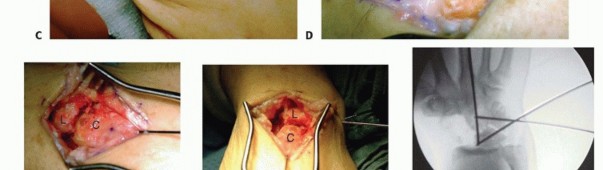

Four-Corner (Capitate-Hamate-Lunate-Triquetral) Arthrodesis Using Kirschner Wire Fixation

TECH FIG 2 • A,B. AP and lateral radiographs showing a circular plate fusion construct. On the lateral view, the plate is nicely seated to prevent dorsal impingement.

TECH FIG 4 • A. Lunotriquetral joint during decortication. (Fingers are at top in all images.) B.

TECH FIG 5 • Scaphocapitate fusion construct using two headless, cannulated compression screws. Note the addition of a radial styloidectomy. (Fingers are at top.)

RADIOCARPAL (RADIOLUNATE) ARTHRODESIS

TECH FIG 6 • A,B. Preoperative AP and lateral radiographs. C,D. Postoperative AP and lateral radiographs following radiocarpal arthrodesis. Under fluoroscopy, correct any preoperative VISI or DISI deformity.A Kirschner wire inserted into the dorsal lunate may be used as a joystick to effect correction.Stabilize the lunate in the reduced position with provisional Kirschner wires from the radius into the lunate.Harvest bone graft from the distal radius or iliac crest and pack the graft tightly into the palmar radiolunate joint.Secure the lunate to the radius with Kirschner wires, headless screws, staples, or small blade plates. Pack the remaining bone graft into the dorsal radiolunate joint.Perform a routine closure and apply a splint.The previously described technique is taken from published data.14,278. Capitolunate ArthrodesisMake a dorsal incision from base of second metacarpal to Lister tubercle.Use the third and fourth extensor interval as described earlier.Perform an inverted “T” capsulotomy to visualize the scapholunate and capitolunate joints. Perform a limited styloidectomy (˜3mm) and excise the proximal pole of scaphoid.Stabilize distal scaphoid to capitate with a Kirschner wire. Alternatively, the entire scaphoid can be excised.Denude the capitolunate articulation.Harvest bone graft from distal radius or iliac crest and pack it into this prepared joint.Tricortical iliac crest graft allows maintenance of carpal height.Assure capitolunate alignment with a Kirschner wire as described earlier for CHLT fusion.Place a guidewire followed by headless screw into proximal ulnar corner of lunate as described earlier for CHLT fusion.Take wrist through a range of motion to be certain a mechanical block is not present. Perform a standard closure and apply a splint.The previously described technique is taken from published data.12,15P.989